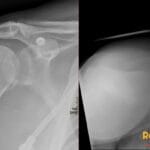

72 yr male with hemodynamically unstable bradycardia and a portable chest radiograph to evaluate device placement.

Diagnosis: Right Internal Jugular Temporary Transvenous Pacemaker

- On a frontal radiograph, the lead tip should be positioned at the apex of the right ventricle, appearing to the left of the spine.

- Radiograph: Shows a radiopaque lead entering via the right internal jugular vein, traveling through the right atrium, and terminating at the right ventricular apex; must be monitored for kinks, fractures, or malposition.